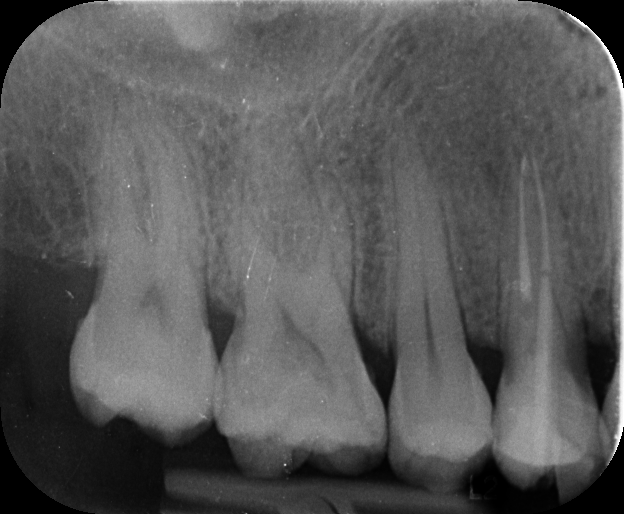

- After one year, the patient returned for a check-up. Clinically, the tooth was healthy, and the fillings were intact.

- A follow-up radiograph showed remarkable healing—about 95% of the lesion had resolved, and the tooth was stable.

- Based on these excellent results, I recommended proceeding with a crown for long-term protection.